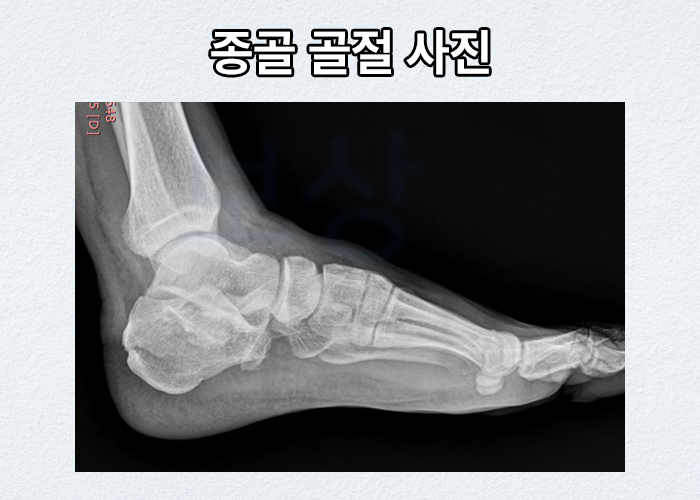

알아보셔야 합니다. 종골의 골절 원인은 대다수 높은 곳에서 떨어지는 추락사고로 인해 빈번히 발생합니다. 종골골절은 큰 외상성 충격을 받기에 분쇄골절의 형태가 많으며, 종골이 위치한 부위 특성상, 거골 손상에 족관절까지 손상되어 향후 외상성 관절염이 올 수 있고 수술까지 진행하신다 해도 저희가 상담한 대다수 환자분들은